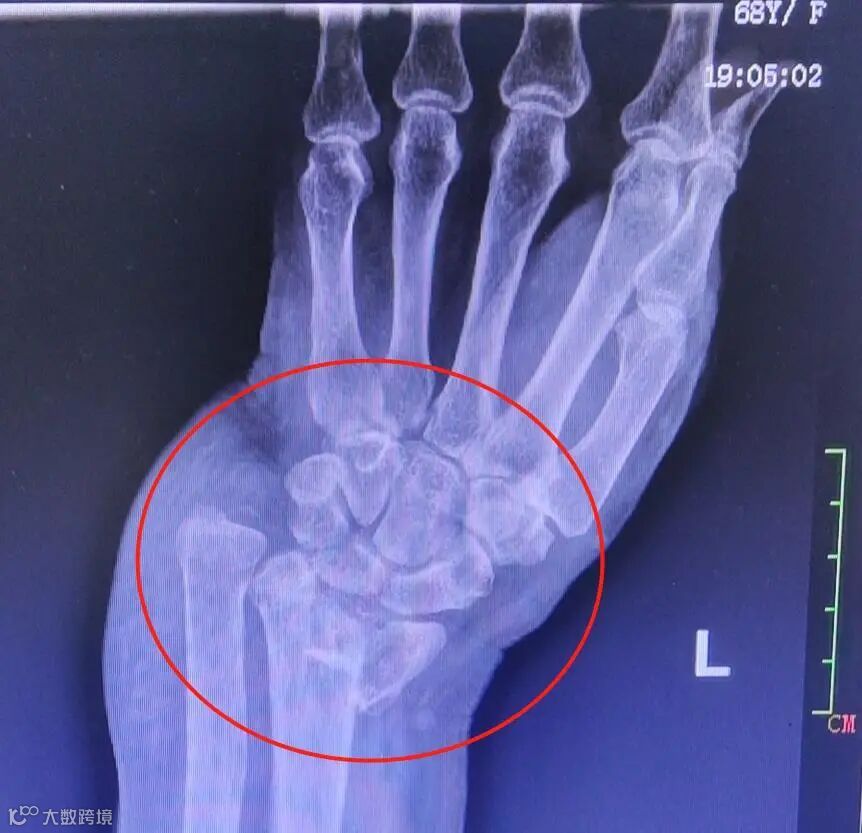

当晚,患者在家人陪同下来到市人民医院急诊科就诊,医生发现患者左手腕部肿胀,左手腕错位弯曲,于是进一步拍片检查受伤情况。经左腕关节DR拍片结果显示骨折严重:左桡骨远端骨折,左尺骨茎完全性骨折、骨折远端移位。

患者到创伤手外骨科病房治疗时,依旧疼痛不止,稍微触碰手腕部便疼痛难忍,五指不能自如

活动